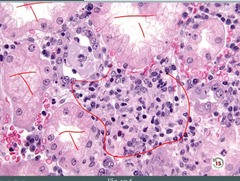

Liquefactive Necrosis

Front

Back